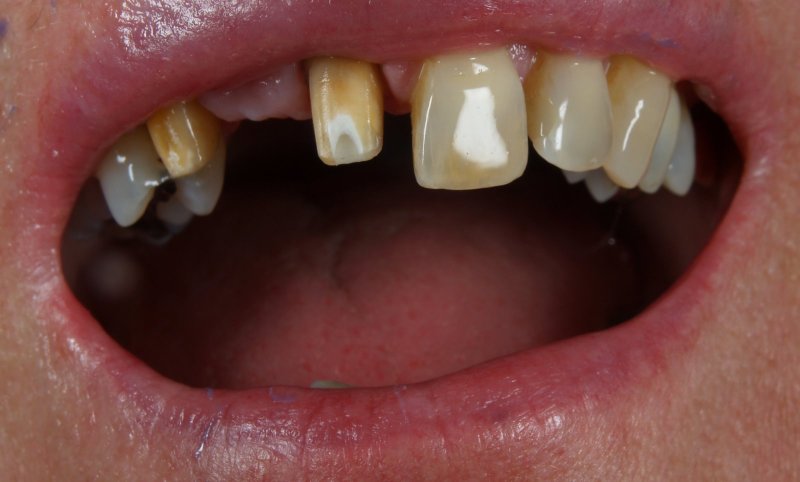

Patientenzufriedenheit